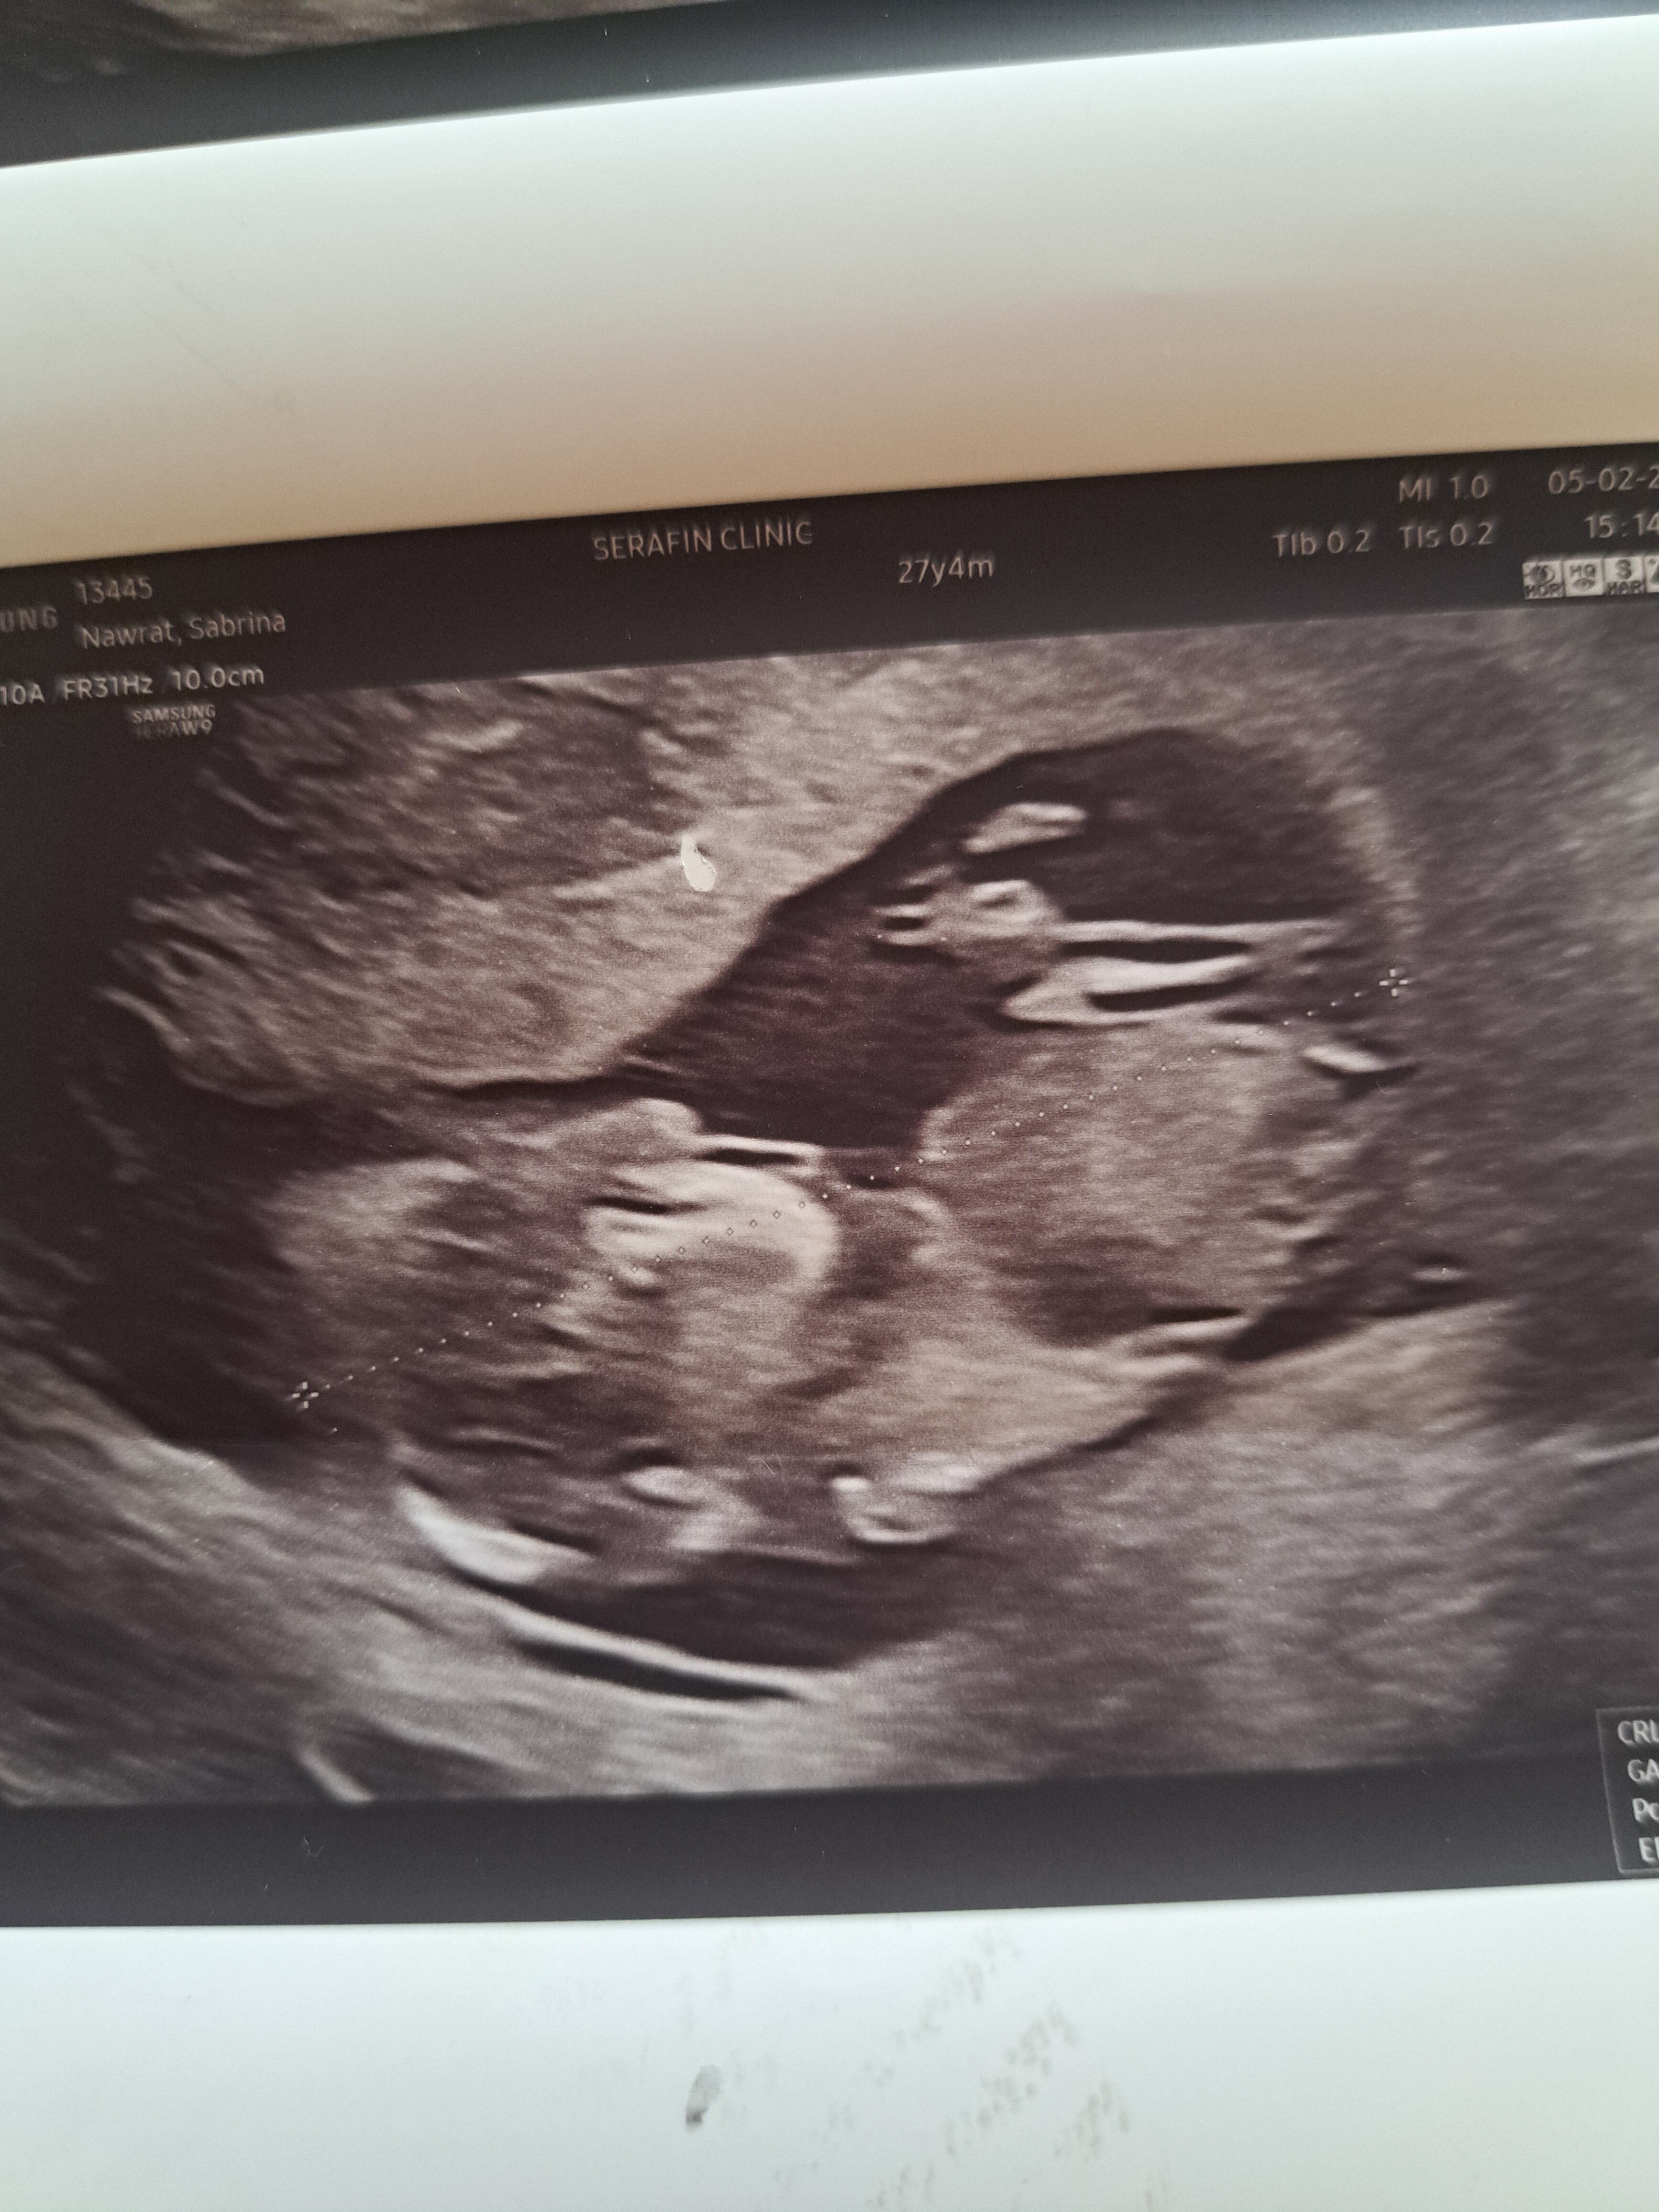

Tu jest tylko głowa i niecały tułów z rączką moim zdaniemHej, wiem że jeszcze troszkę trzeba poczekac ale może jest ktoś kto zna się na tym i potrafi odczytać płeć, to moje 3 dziecko i mi to wygląda na dziewczynkę ale może uda się komuś coś wiecej zobaczyc?

Tu jest tylko głowa i niecały tułów z rączką moim zdaniemNie ma dolnej części ciała z wyrostkiem do oceny.

Jest pod takim kątem, że nie widzę tu wyrostka, ale my nie jesteśmy lekarzamiTo jest zdjęcie calego dziecka bo na tym lekarz mierzył długość dziecka